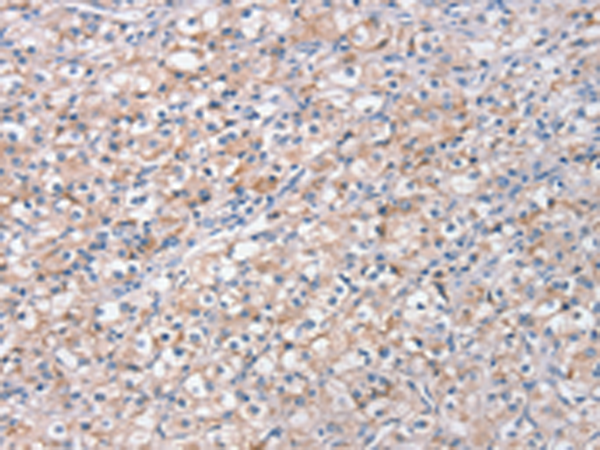

分类: 科研抗体货号: P08839别名: HDL4; GTF2D; SCA17; TFIID; GTF2D1应用: WB,IHC反应种属: Human